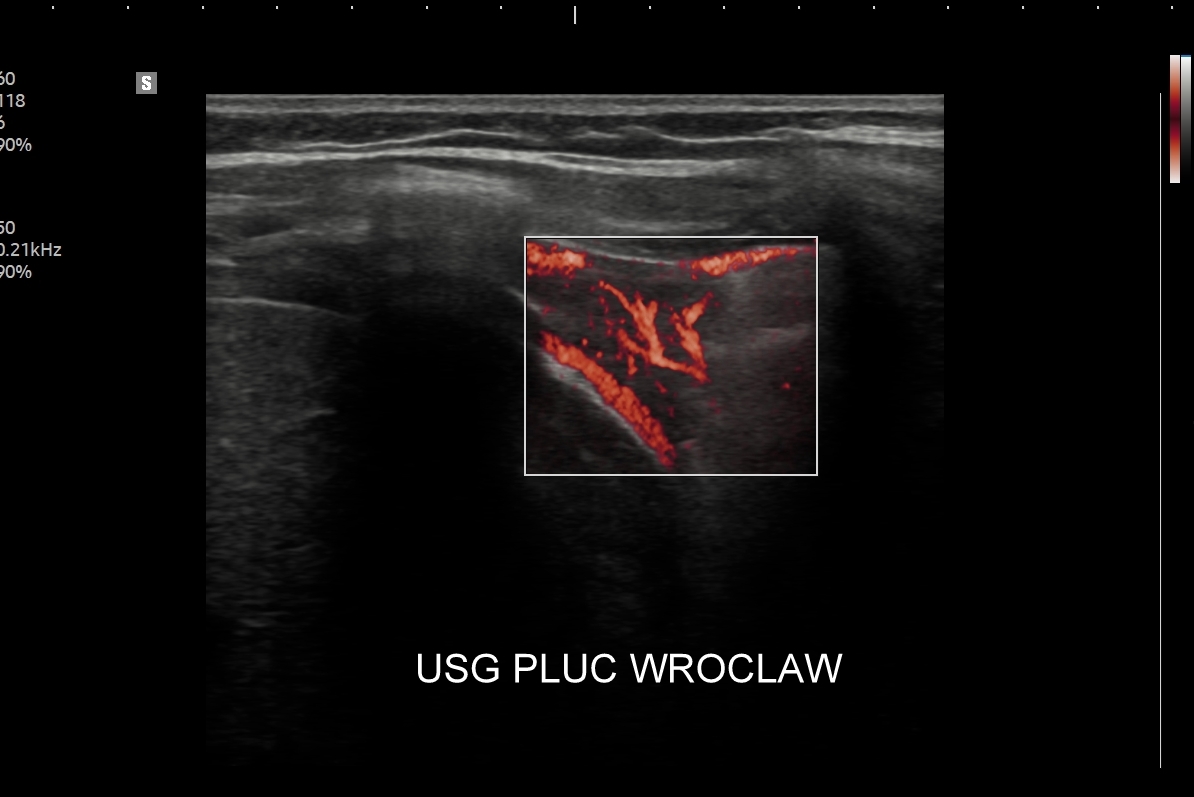

Specjalista chorób wewnętrznych. Absolwent Akademii Medycznej we Wrocławiu w 2000 r. Zwolennik nowoczesnych technologii i pionier niestandardowych zastosowań USG w Polsce, w tym użycia obrazowania mikroprzepływów w obrazowaniu płuc, czy badań USG z kontrastem. Na początku lat 2000-ych był jednym z pierwszych lekarzy, który wdrażali szerokie zastosowanie USG w intensywnej terapii. W praktyce ambulatoryjnej wprowadził do regularnego użycia kompleksowe badanie USG klatki piersiowej, płuc i serca. Posiada wieloletni staż kliniczny i szkoleniowy w Polsce oraz zagranicą (Wielka Brytania, Niemcy, Austria, Włochy, Rumunia). Wykonał ponad 40.000 badań USG. Dydaktyk i nauczyciel młodego pokolenia lekarzy w Polsce i Europie.